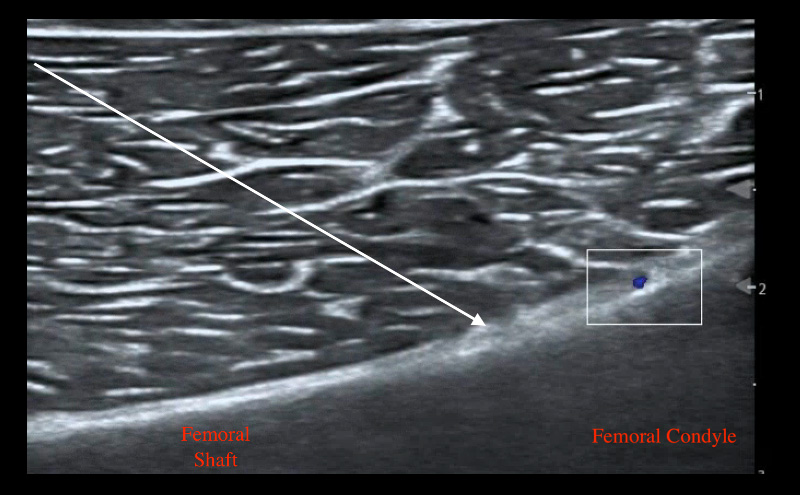

To target the SMGN, place the transducer on the medial aspect of the distal femur with the probe marker facing superiorly and identify the femoral shaft and femoral condyle. Another approach would be starting at the knee joint and moving superiorly to identify the femur bone. As the femoral shaft slopes superiorly, place color Doppler to identify the superior medial genicular artery. Advance a 20 gauge needle (or smaller) toward the slope avoiding the artery and make contact with bone. Inject 3-5 mL of local anesthetic lifting soft tissue and spreading along the periosteum.

Figure 3: SMGN ultrasound anatomy with needle trajectory indicated by arrow